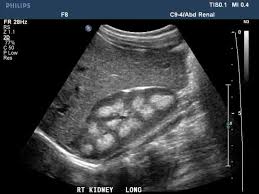

Kidney Normal Vs Abnormal Abdominal Ultrasound

1 2 b mode shows axial section of a left kidney with normal.

Related pathology a discrepancy of 2 cm between renal lengths should be considered abnormal 10 and may indicate an underlying disease. Depending on location colon sigmoid and the patient s build slender vs obese an infected diverticulum may or may not be visible. The kidney will lie obliquely in the ipsilateral iliac fossa. 1 1 b mode shows longitudinal section of a left kidney with normal volume and echostructure and bipolar diameter of 11 3 cm in axial scans acquired at the renal hilum the transverse diameter measures between 5 and 6 5 cm median 5 7 cm fig.